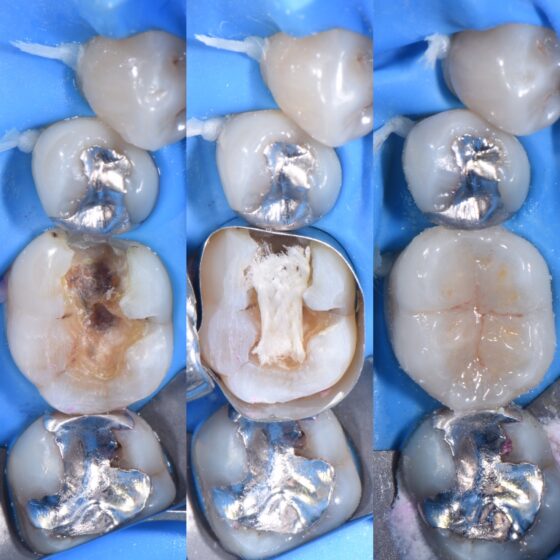

宇部市歯医者 虫歯治療をラバーダム防湿下で行いました。歯の神経を守る...